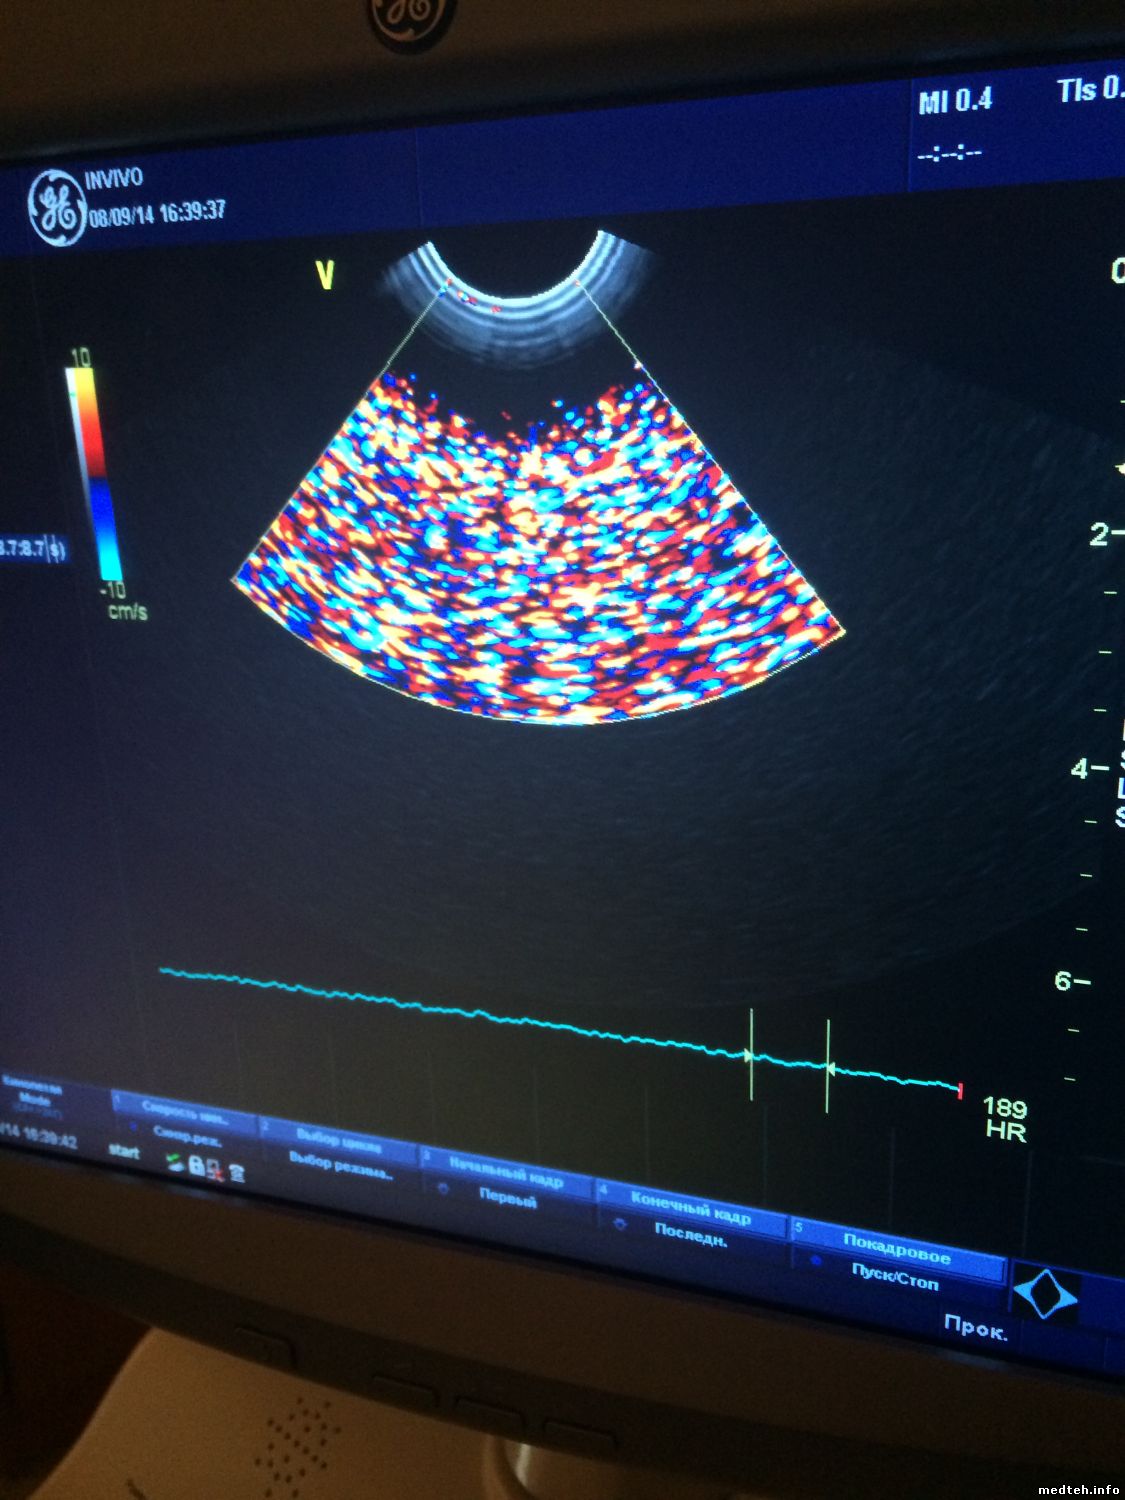

Подскажите, вот такой артефакт.

Когда включаешь вагинальный датчик в доплеровском режиме, происходит вот такой прикол!

В остальных режимах всё ОК!

Все перепробывл! все элект.устролйства убрал! в другую комнату вытащил! бесполезно! датчик тупо на воздухе идут помехи!!!!!